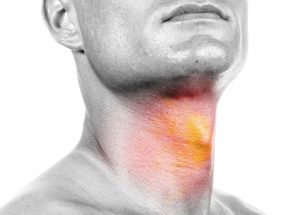

Management of head and neck infections Emergency treatment of all head and neck infections. A tooth abscess is a pocket of pus that’s caused by a bacterial infection. The abscess can occur at different regions of the tooth for different reasons. A periapical abscess occurs at the tip of the root. The most common source of infections in the head and neck area is a tooth abscess. A periapical tooth abscess occurs when bacteria invade the dental pulp — the innermost part of the tooth that contains blood vessels, nerves and connective tissue. Bacteria enter through either a dental cavity or a chip or crack in the tooth and spread all the way down to the root. The bacterial infection can cause swelling and inflammation at the tip of the root. Leaving a tooth abscess untreated can lead to serious, even life-threatening, complications. Symptoms may include:

- Severe, persistent, throbbing toothache that can radiate to the jawbone, neck or ear

- Swelling in your face or cheek

- Tender, swollen lymph nodes under your jaw or in your neck

Do not ignore the important signs of pain and fever, as they usually indicate the likelihood of a significant infection. In many cases, the symptoms can be treated with antibiotics and warm saltwater rinses. However, in serious cases, the abscess may need to be lanced (incised) and drained. It is important that one seeks medical help at the first signs of an abscess to prevent the condition becoming more serious. In extreme cases a small infection can spread down the throat, and can even travel to the chest cavity. Where the upper teeth are affected, the infection usually spreads to the cheek and the area under the eye. Some of the veins in this area do not have valves, so blood can flow backward and in extremely severe cases, spread infection to an area under the brain, known as the cavernous sinus.